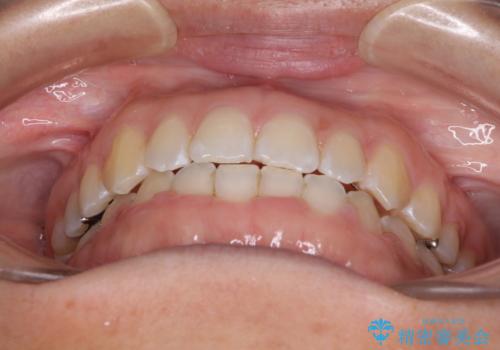

前歯の隙間を閉じたい 短期間でのワイヤー矯正

- 上の前歯の隙間を気にして来院された患者様です。

インビザラインの自己管理は自信がないとのことで、ワイヤー矯正により隙間を閉じていくこととしました。

下の前歯が上の前歯を突き上げるように咬合するため、咬み合わせの位置を改善しながら隙間を閉じていきました。

元々の歯並びが悪くなかったため、9ヶ月で綺麗に仕上がりました。